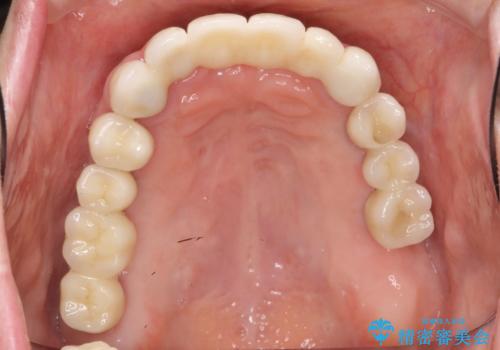

歯周病 全顎治療

- 前歯の見た目、入れ歯による噛めないことの改善を求めて来院されました。

検査により全顎的な歯周病治療、欠損のインプラント補綴、根管治療が必要な状態であることをお伝えし、治療を計画します。

全体的な歯周病が認められる場合、歯を失った一部のみの治療となることはほぼありません。

失ってしまった機能を回復し、今後歯を失わないよう残せる歯に歯周病治療を行い、安定した咬合を確立することで長期的に問題なく噛めるような口腔内環境を達成できるようになると考えます。